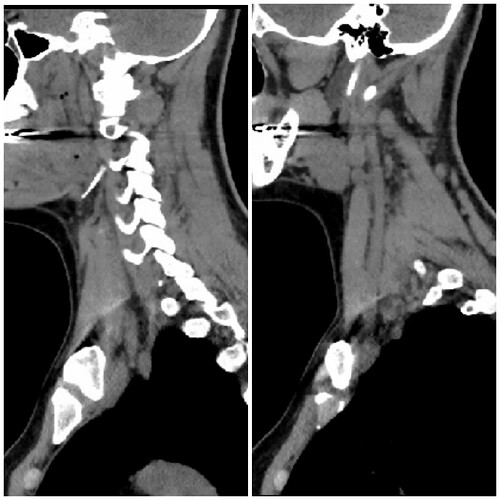

I’ve annotated one of your images but am not sure if your right side is the left image & your left side is the right or vice versa. You have one styloid that is visible along w/ C1 but the other is hidden in the very white area near your skull base on the other side (I labeled about where it should be).

On on side (left?) it looks like your styloid may be causing some compression of your internal jugular vein. On the other side (right?), it appears either you have a significant section of calcified stylohyoid ligament or the greater horn of your hyoid is elongated. Either way, it appears you have some vascular compression

on that side as well. Usually when compression occurs down that low, it’s the internal or external carotid artery that is getting poked.

The axial image you posted is good but I can’t see much of significance because you didn’t get contrast, however, some of your larger veins/arteries appear to be visible in the sagittal images you posted.

@Jete without contrast it’s hard to tell for sure but I’ve put red line/dots around what I think is your IJVs. Your left (right side of image) looks to be more compressed than your right.